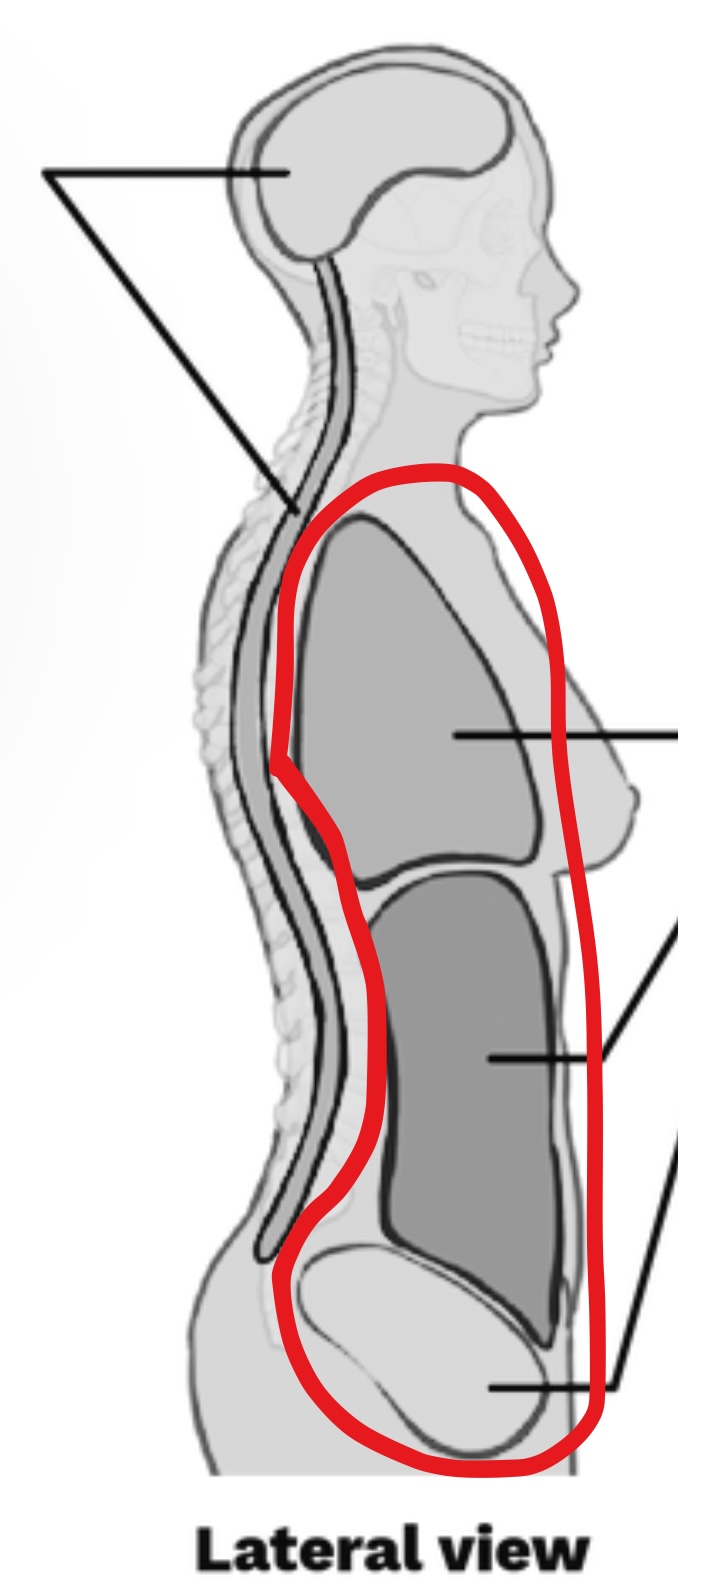

What cavity is this?

Ventral body cavity